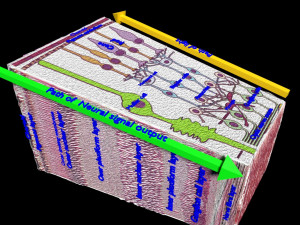

This is a 1:1 scaled model of right breast cut opened in sagittal plane to reveal its internal antomy and histology (schematic). The deeper parts and fascial layers are also depicted to give a very detailed approach to the model. The full layers starting from skin, nipple areola, till intercodtal muscles and ribs are also depicted.